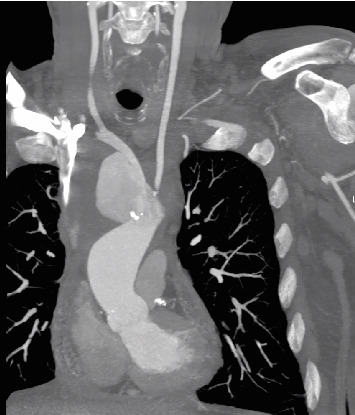

An infection and aortic arch pseudoaneurysm can be fatal if not emergently and adequately treated. Optimal surgical procedures and optimal graft materials remain controversial. We describe a 61-year-old patient who underwent in situ repair of the infected pseudoaneurysm of the aortic arch. A porcine pericardium patch (BioIntegral Surgical Inc., Mississauga, ON, Canada) was used to reconstruct the aortic wall, followed by the reconstruction of the brachiocephalic trunk using a surgeon-made tube. The patient made a full recovery. Self-made tube grafts for in situ reconstruction offer many advantages and may be a valuable option.

Abstract Image